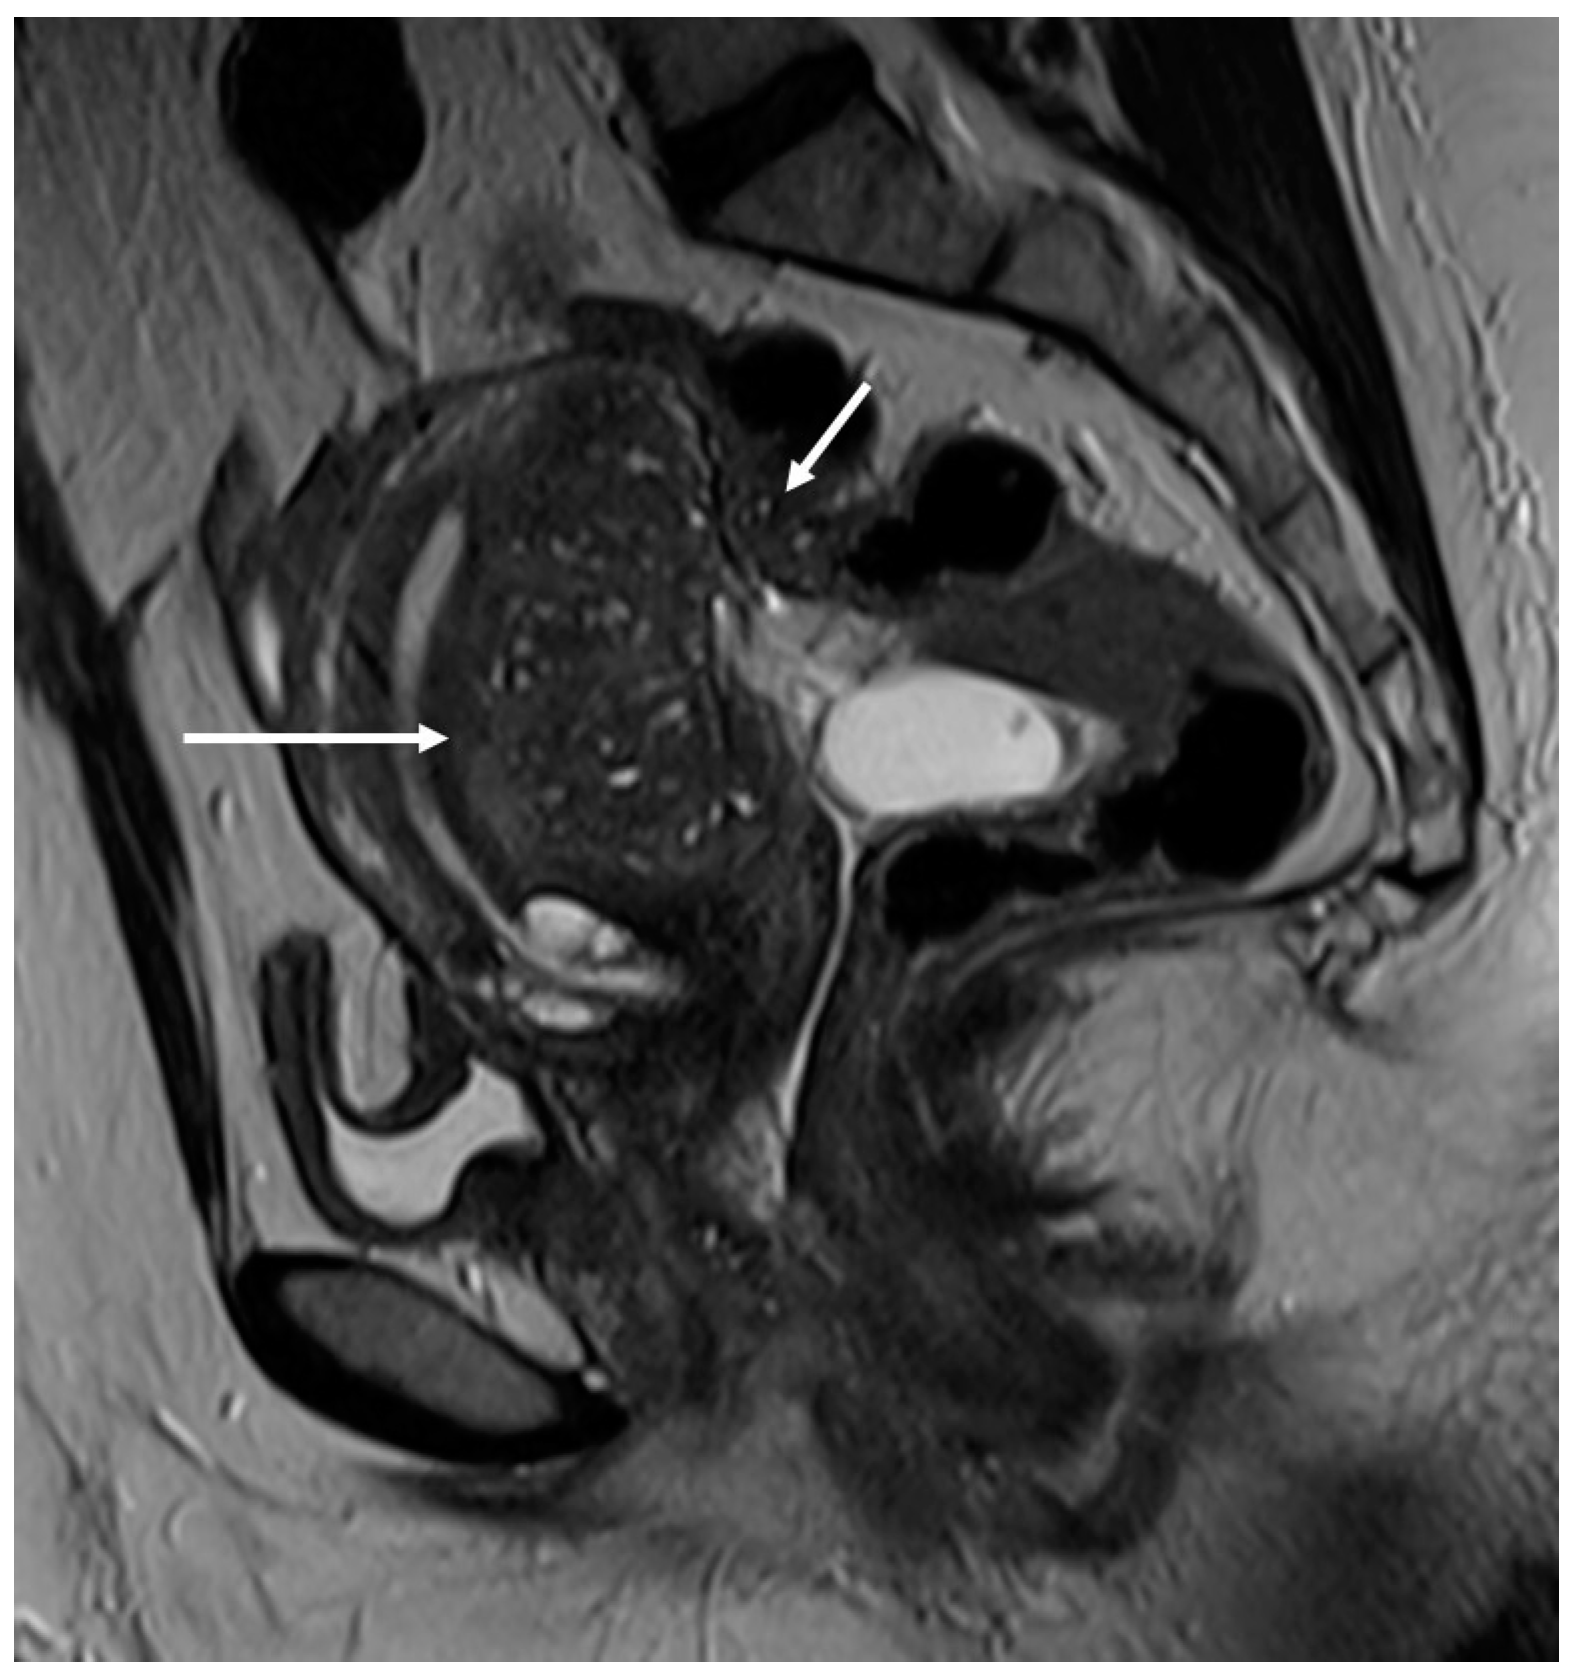

In other cases, the involvement of the round ligament can be appreciated as irregular contours with a nodular aspect [43] (Figure 2).

Figure 2.

Deep infiltrating endometriosis of the anterior and posterior compartments in 33-year-old female with dysmenorrhea, chronic pelvic pain, dyspareunia and dyschezia. (A) Sagittal T2WI. Evidence of external anterior adenomyosis and plaque of the vesico-uterine pouch (white arrow); (B) Sagittal T2WI. Retrocervical localization of DIE (white arrow); (C) Axial T2WI. Left uterosacral ligament (USL) localization (white arrowhead), plaque of vesico-uterine pouch (white arrow) with involvement of the round ligaments, particularly on the left (white dotted arrows), and adhesions with the ovaries (retraction of the broad ligaments).

The surgical approach can vary according to the proximal or distal involvement [39].

Involvement of the proximal portion of ligaments (distance less than 2 cm from the cervix) may, in some cases, be associated with thickening at the level of the torus uterinus; in such cases, it is essential to report any mass or thickening in the upper portion of the posterior cervix, as this could cause the surgeon to proceed with a laparoscopic trans-vaginal approach [7] (Figure 2, Figure 3 and Figure 4).

Figure 3.

Right uterosacral ligament localization in a 43-year-old female. The right uterosacral ligament appears thickened at uterine insertion (white arrow).

Figure 4.

Retrocervical endometriosis plaque, intestinal localization, kissing ovaries with bilateral ovarian endometriomas. (A,B) Axial T2WI; (C) Coronal T2WI. Hypointense retrocervical plaque (white arrowhead in (A)) localized in the uterine torus with involvement of the utero-sacral ligaments. Adhesions involve both ovaries with bilateral endometriomas (white arrows), which are prolapsed in a retro-uterine position and adhered to the utero-sacral ligaments and the recto-sigmoid junction. There is also an eccentric anterior parietal thickening in the recto-sigmoid junction suggestive of intestinal endometriosis lesion (white dotted arrow in (A)).